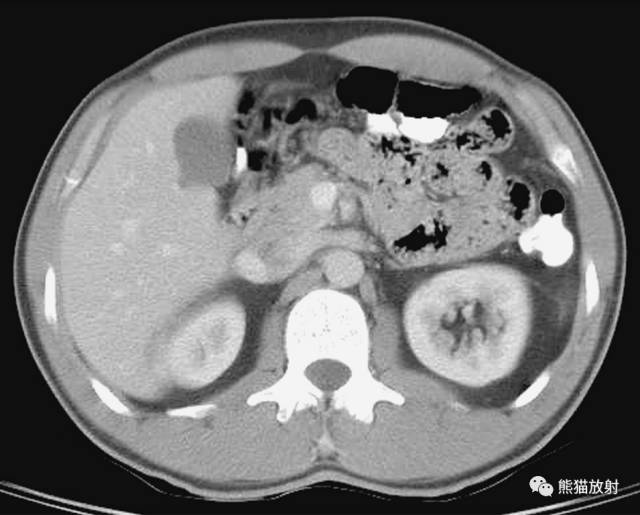

第三层

1、肝右叶;2、肝尾状叶;3、下腔静脉;4、肝门静脉;5、腹直肌;6、肝圆韧带;7、肝左叶;8、十二指肠降段;9、腹白线;10、肠系膜上动脉;11、腹腔干;12、胃;13、脾静脉;14、胰腺;15;空肠;16、横结肠;17、降结肠;18、左结肠静脉;19、腹外斜肌;20、膈肌;21、奇静脉;22、髂肋肌(胸段);23、胸导管;24、胸椎;25、棘肌;26、椎管和脊髓;27、腹主动脉;28、半奇静脉;29、最长肌;30、肾上腺动脉;31、左侧肾上腺;32、左肾;33、左肺;34、背阔肌;35、脾脏;36、肝门区;37、圆韧带凹痕;38、肝十二指肠韧带;39、网膜孔;40、网膜囊/大网膜;41、胰淋巴结;42、右膈下隐窝;43、肝淋巴结;44、腰淋巴结;45、膈上淋巴结;46、后纵隔;47、脾门;48、左结肠旁沟。